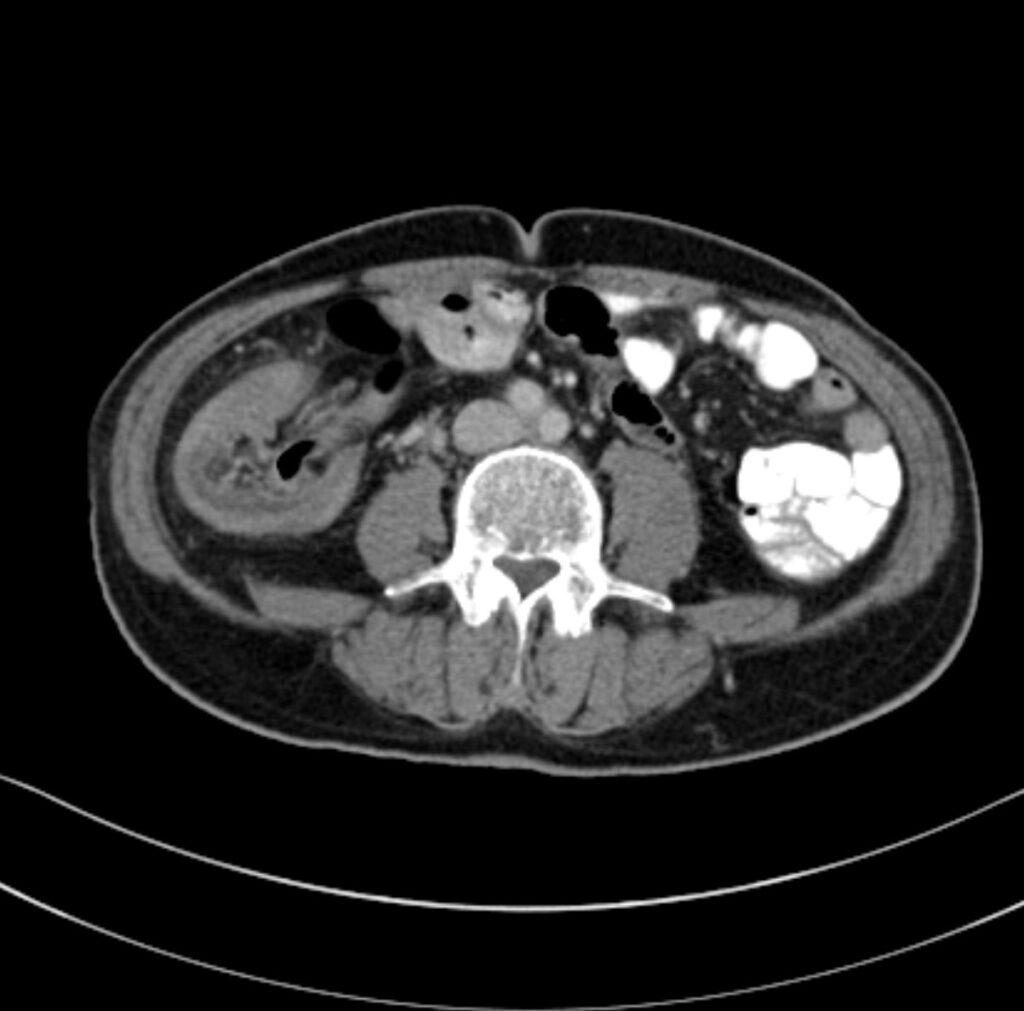

*70-year-old male with abdominal pain and vomiting.

What is the most likely diagnosis?

Ileocolic intussusception

CT images of abdomen revealed the bowel-in-bowel sign in the right lower quadrant with layering of bowel wall and mesenteric fat.

The most common type of intussusception is ileocolic (90%). Ultrasound signs include the target sign and pseudokidney sign.